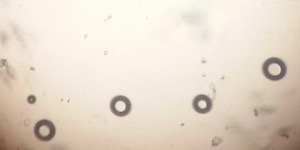

Preparation of niosomes from proniosomes and morphological evaluation (Photomicroscopy)

The optical photographs of all reconstituted proniosomal formulae are shown in fig. (1-28). The photographs revealed that the formed niosomes are unilamellar vesicles with a spherical shape and smooth surface. The vesicles were insular and separate without aggregation or lumping. Apparently, proniosomal formulae containing span 40 and span 60 yielded vesicles of large numbers with well-identified outline and core which will affect the entrapment efficiency of loaded drug directly. However proniosomal formulae containing span 20 and span 80 produced small numbers of vesicles with a slightly different outline. This may be due to the high phase transition temperatures of both span 40 and span 60 which will cause the formation of a large number of stable niosomal vesicles. The phase transition temperatures for span 20, 40 and 60 are 16, 42 and 53 °C; respectively, however, span 80 possess the lowest phase transition temperature at 12 °C [35]. This explains why proniosomal formulae containing span 20 and span 80 produce small numbers of vesicles upon hydration.